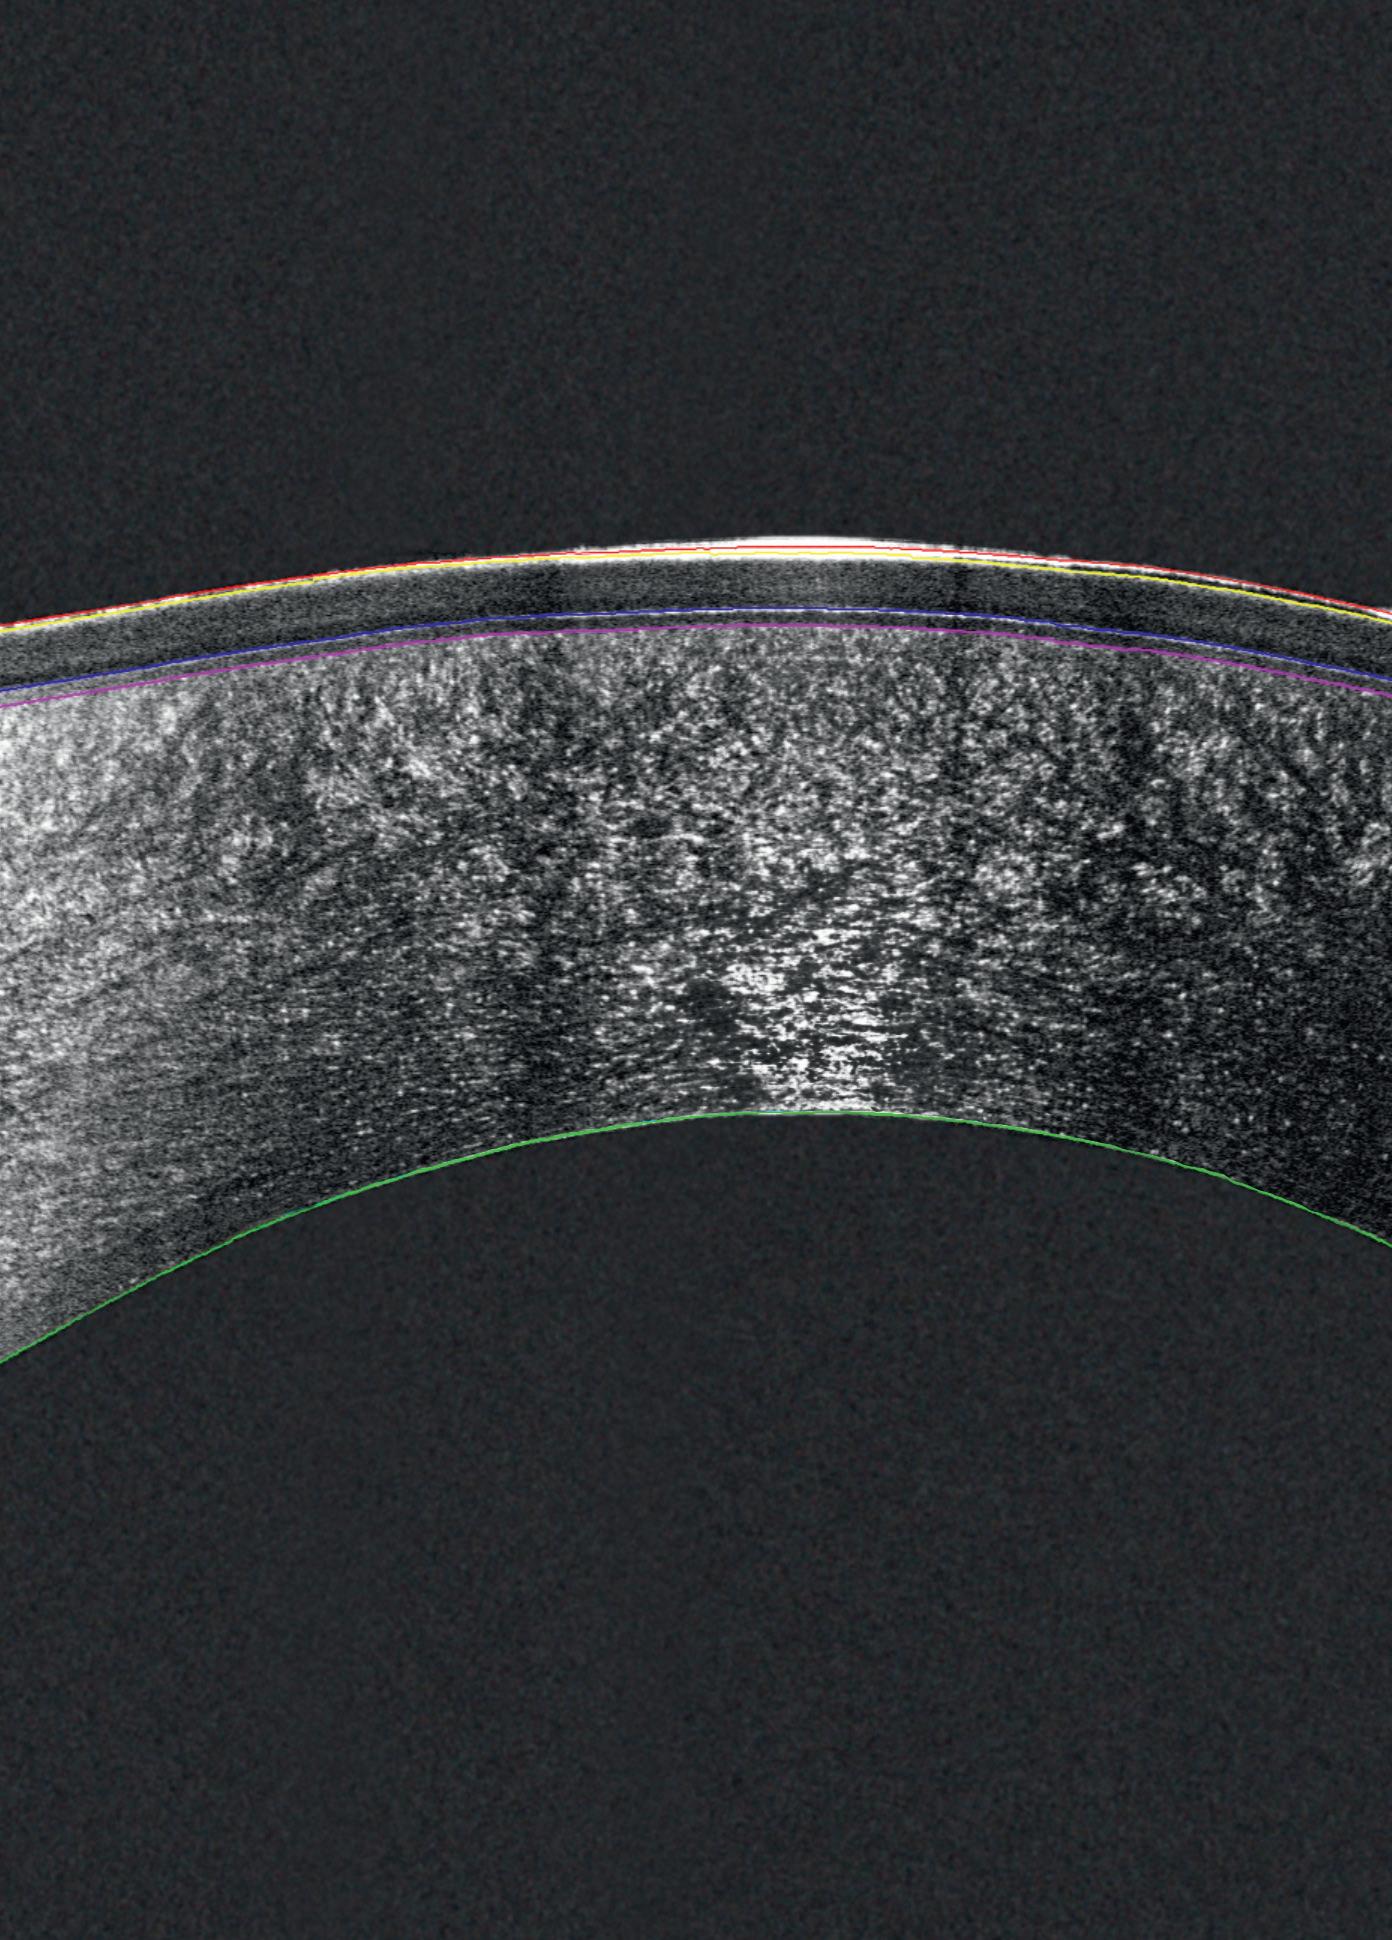

Combining the proven power of Scheimpflug imaging with the precision of ultra high-resolution OCT enables the detection of previously unseen corneal pathologies with unprecedented clarity.

Diagnose earlier. Treat smarter. Care deeper.

EPITHELIUM

BOWMAN’S LAYER

STROMAL LAYER

The Pentacam® Cornea OCT can increase the confidence that your diagnosis is correct.